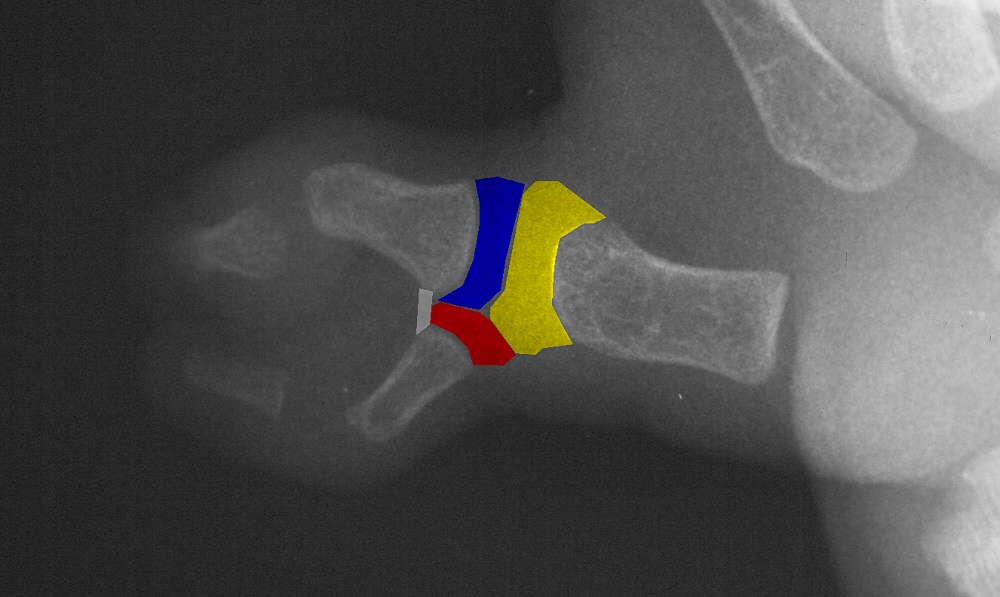

| Case 1. Wassell IV duplication of the proximal and distal phalanges, with characteristic deviation of the thumbs away from each other at the MCP and toward each other at the IP joints. This was corrected by metacarpal head narrowing, opposing closing wedge osteotomies of the metacarpal and proximal phalanx and collateral ligament reconstruction using parts from the deleted digit. |